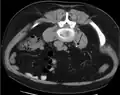

Calcium-containing stones are relatively radiodense (opaque to X-rays), and they can often be detected by a traditional radiography of the abdomen that includes the kidneys, ureters, and bladder (KUB film).[59] KUB radiography, although useful in monitoring size of stone or passage of stone in stone formers, might not be useful in the acute setting due to low sensitivity.[60] Some 60% of all renal stones are radiopaque.[61][62] In general, calcium phosphate stones have the greatest density, followed by calcium oxalate and magnesium ammonium phosphate stones. Cystine calculi are only faintly radiodense, while uric acid stones are usually entirely radiolucent.[63]

Otherwise a noncontrast helical CT scan with 5 millimeters (0.2 in) sections is the diagnostic method to use to detect kidney stones and confirm the diagnosis of kidney stone disease.[16][57][61][66][7] Near all stones are detectable on CT scans with the exception of those composed of certain drug residues in the urine,[59] such as from indinavir.

Where a CT scan is unavailable, an intravenous pyelogram may be performed to help confirm the diagnosis of urolithiasis. This involves intravenous injection of a contrast agent followed by a KUB film. Uroliths present in the kidneys, ureters, or bladder may be better defined by the use of this contrast agent. Stones can also be detected by a retrograde pyelogram, where a similar contrast agent is injected directly into the distal ostium of the ureter (where the ureter terminates as it enters the bladder).[61]